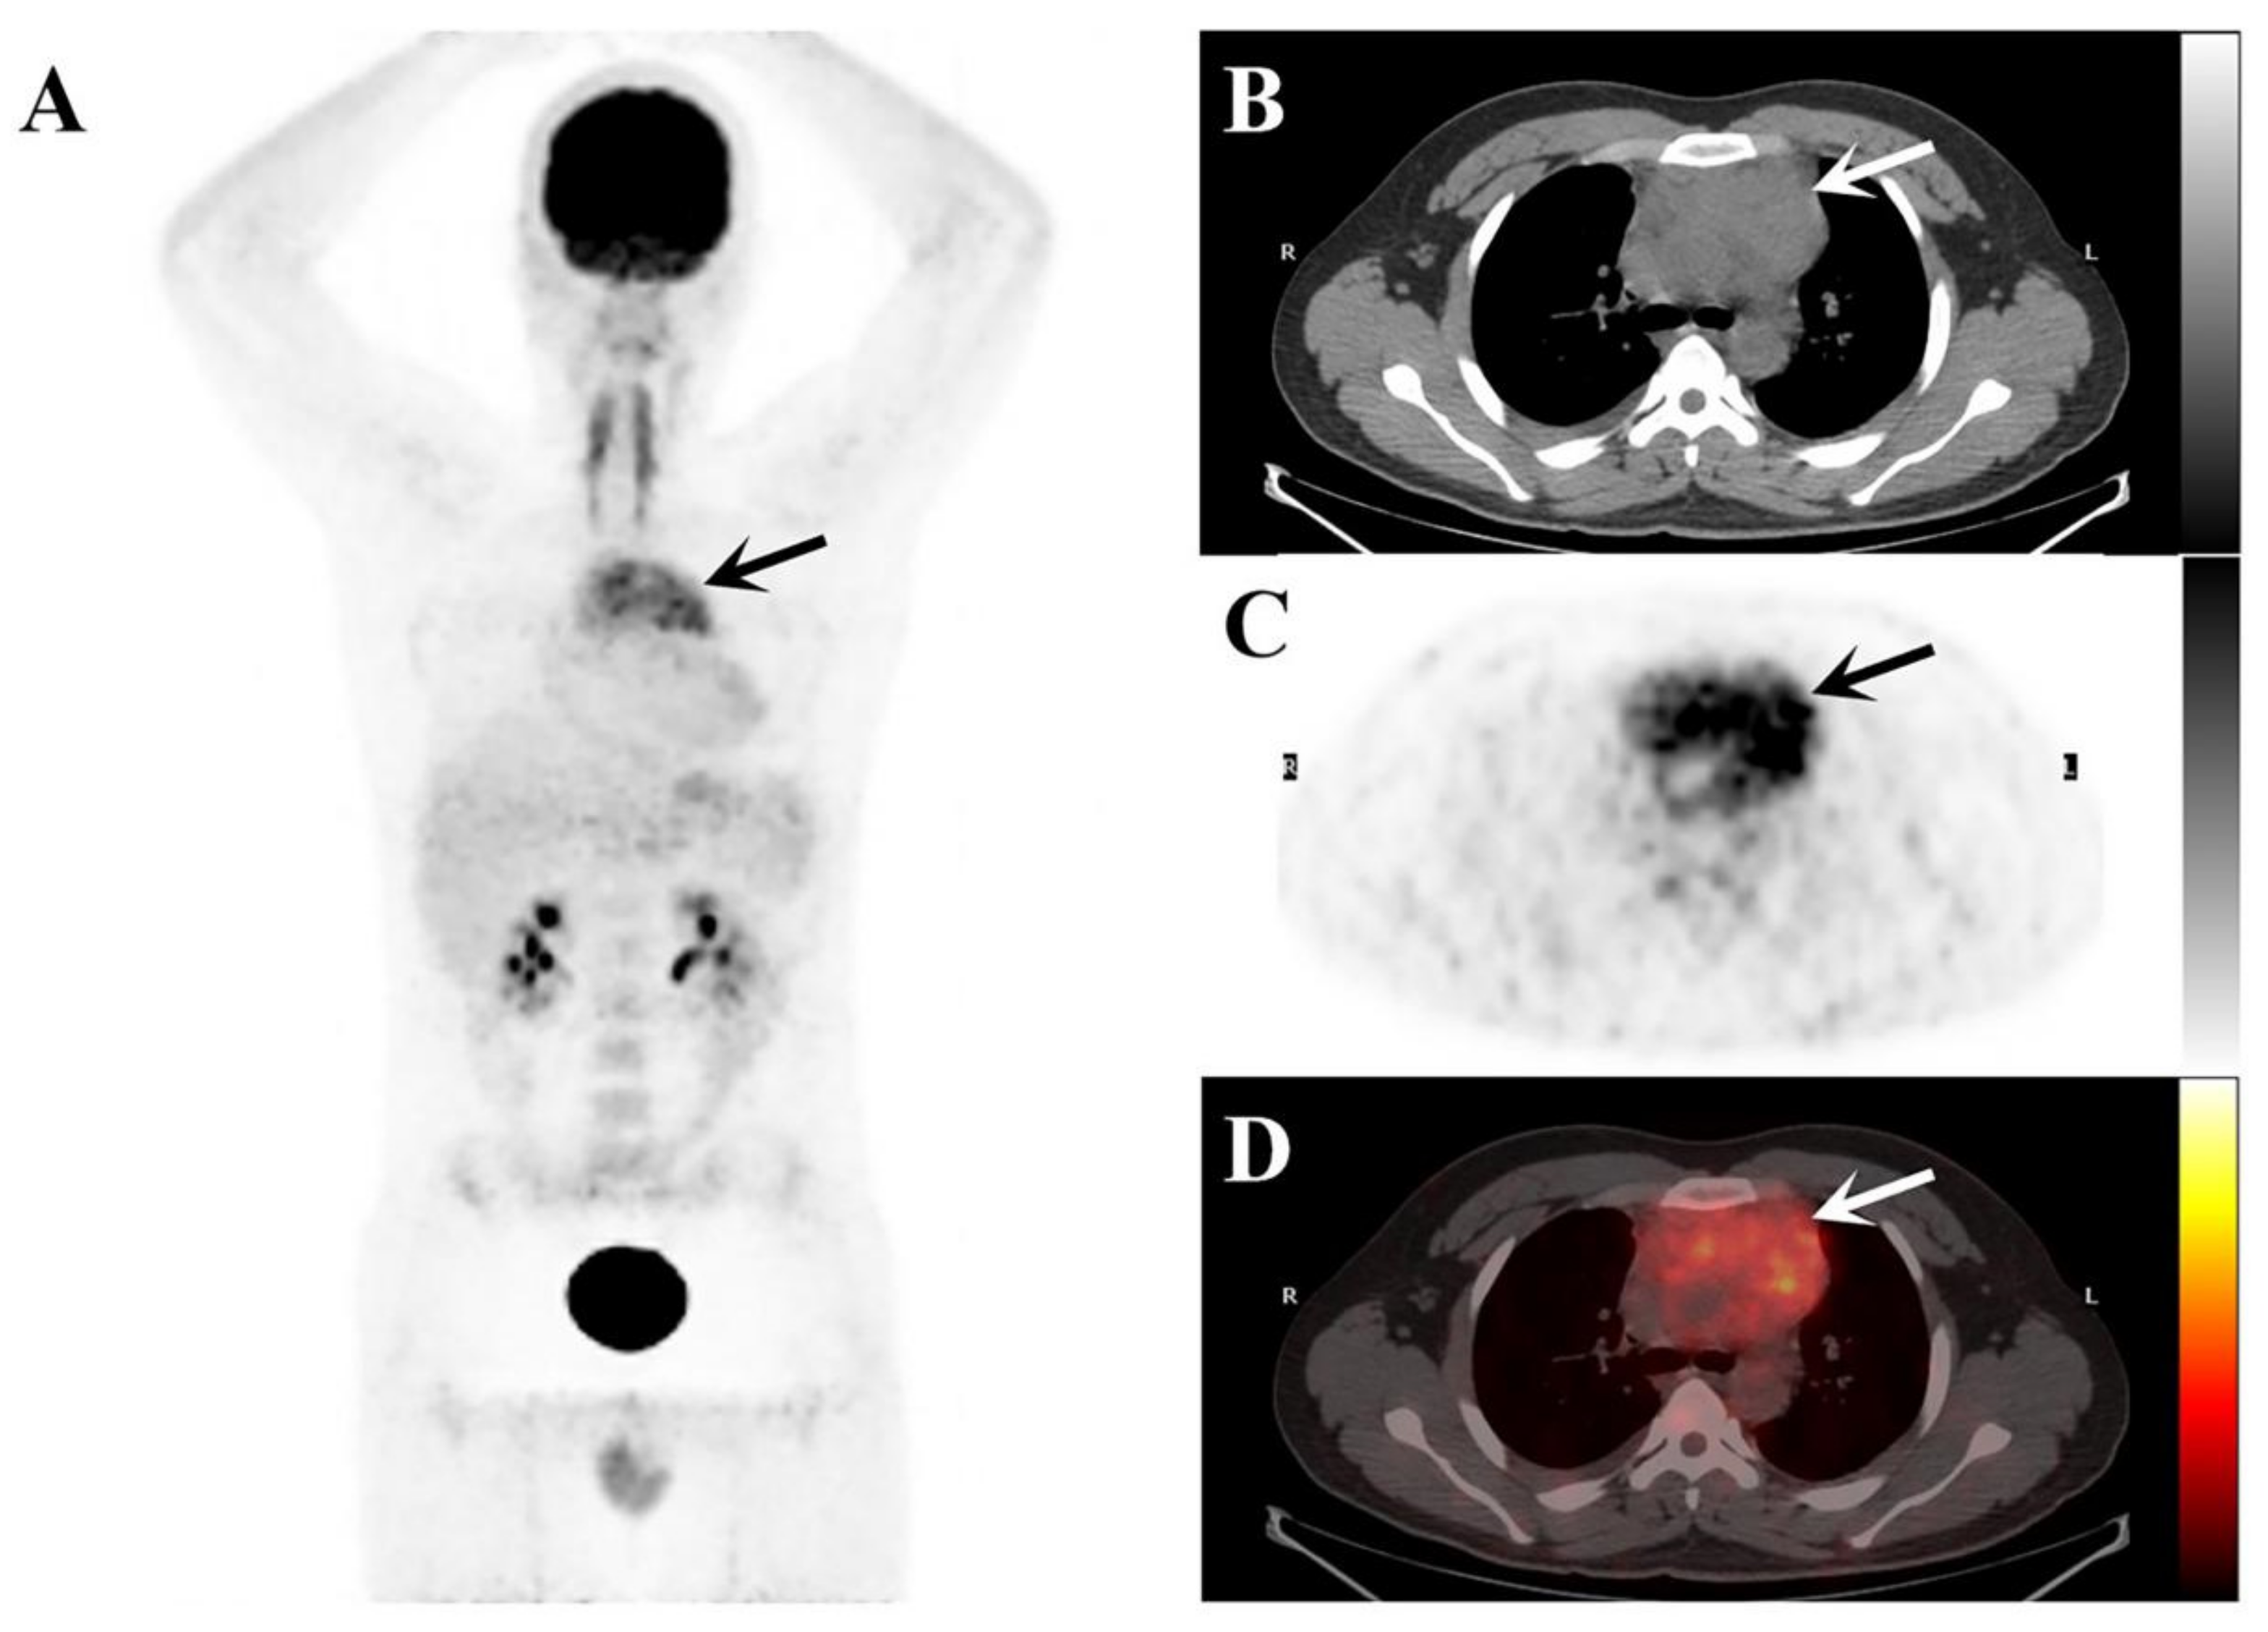

2. Case Presentation